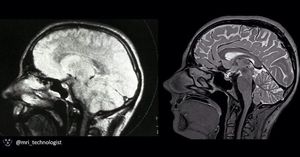

Early brain MRI scan from the 1980s (left) and nowadays high resolution 3D T2-w TSE (right) acquired at 3.0 Tesla, Siemens Prisma.